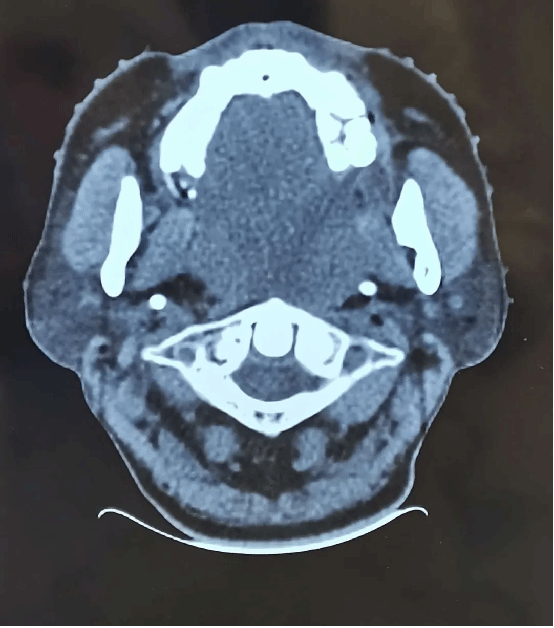

治疗后

放疗过程中,医护团队全程密切监测路先生的身体反应,及时调整治疗细节,给予专业的护理指导与心理支持。随着放疗周期推进,奇迹逐渐显现:肿瘤开始逐步缩小,气道压迫症状明显缓解,路先生的呼吸越来越顺畅。治疗结束后复查显示,肿瘤体积较治疗前显著缩小,气道通畅度恢复正常——他终于能平躺在床上,安然进入久违的深度睡眠。